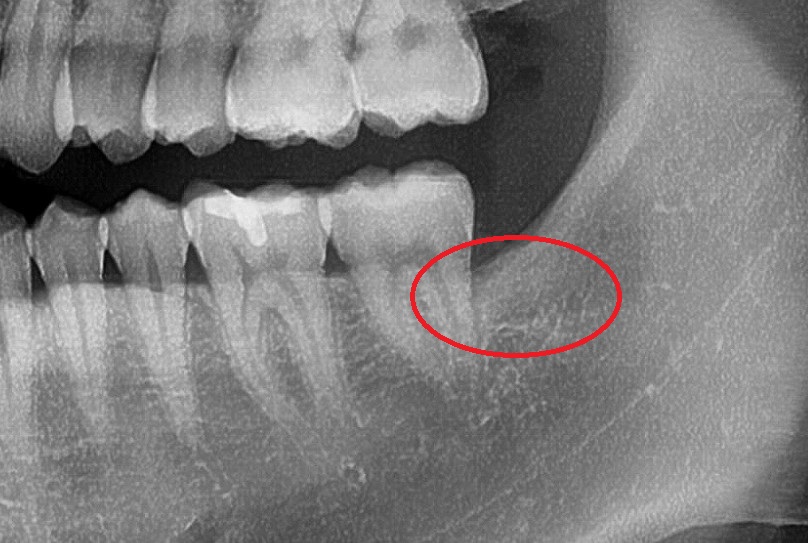

저렇게 사랑니가 누워서 옆에 치아와 붙어있는 경우에는

사랑니 발치 후 옆 치아 뿌리가 노출이 될 수 있기 때문에

잇몸 치유가 느린 경우 노출된 부위가 시릴 수 있습니다.

치아머리의 일부만 밖으로 노출된

사랑니는 그 주변 잇몸이 자주 부을 수 있기 때문에

양치를 할 때 그 부위도 꼼꼼히 닦아주시는 것이

주변 치은염을 예방하는데 아주 중요합니다.^^